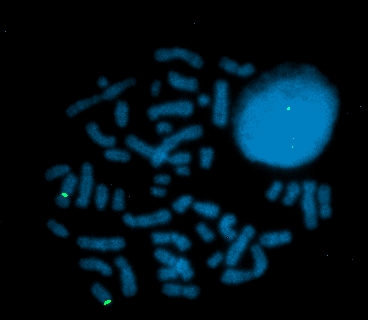

FISH FITC detects D12S2343, DAPI counterstain |